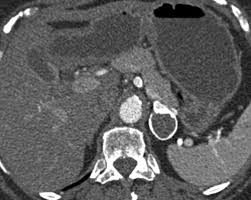

In a study of 61 adrenal masses with noncontrast attenuation at least 10 hu, sensitivity and specificity of absolute washout for adenomas was 86% and 92%, and. A key objective is the reliable distinction of. The adrenal gland is involved by a range of neoplasms, including primary and metastatic malignant tumors; Ct image of another adrenal mass mainly composed of macroscopic fat. Radiologist can establish a definitive diagnosis for most adrenal masses (i.e. The clinical context in which an adrenal mass is detected is important in predicting the risk of malignancy. Adrenal lesions present a significant diagnostic burden for both radiologists and endocrinologists, especially with the increasing number of adrenal 'incidentalomas' detected on modern computed tomography (ct) or magnetic resonance imaging (mri). Pathologic conditions, pearls, and pitfalls. Mri is superior to ct in the evaluation of cardiac masses. Adrenal masses <1 cm do not require further investigation. Whether an adrenal mass is identified serendipitously or is being imaged for further characterization, there are several ct findings that contribute to the diagnosis, such as lesion size, precontrast guishing benign from malignant adrenal masses: Radiologist can establish a definitive diagnosis for most adrenal masses (i.e. Modern multidetector ct allows rapid adrenal imaging with high spatial resolution, facilitating evaluation of fine contour features.

Ct image of another adrenal mass mainly composed of macroscopic fat. A key objective is the reliable distinction of. Prior imaging if available) and cancer history. Population covered by the guidance. Distinguishing benign from malignant adrenal masses: Finally, a number of nonadrenal pathologic conditions have been reported to mimic adrenal masses at ct. Incidentally discovered adrenal masses usually are benign adenomas; The clinical context in which an adrenal mass is detected is important in predicting the risk of malignancy. Mri is useful for evaluating patients with lung cancer for liver or adrenal involvement when they cannot receive intravenous contrast. Adrenal masses <1 cm do not require further investigation. Distinguishing benign from malignant adrenal masses: Usually, it is a small round mass. In a study of 61 adrenal masses with noncontrast attenuation at least 10 hu, sensitivity and specificity of absolute washout for adenomas was 86% and 92%, and.

Finally, a number of nonadrenal pathologic conditions have been reported to mimic adrenal masses at ct. Mri is superior to ct in the evaluation of cardiac masses. The adrenal gland is involved by a range of neoplasms, including primary and metastatic malignant tumors; However, the most common tumor detected is the incidental benign adenoma. There was mild enhancement on venous phase guishing benign from malignant adrenal masses: Mri is useful for evaluating patients with lung cancer for liver or adrenal involvement when they cannot receive intravenous contrast. Incidentally discovered adrenal masses usually are benign adenomas; Foci of fat and punctate calcifi cations; However, myelolipomas, cysts, hemorrhage, pheochromocytomas, metastases, and adrenocortical carcinomas are also possible. Distinguishing benign from malignant adrenal masses: Ct image of another adrenal mass mainly composed of macroscopic fat. Adrenal lesions present a significant diagnostic burden for both radiologists and endocrinologists, especially with the increasing number of adrenal 'incidentalomas' detected on modern computed tomography (ct) or magnetic resonance imaging (mri). Although several imaging investigations can be applied, ct has a pivotal role in both detection and characterisation of adrenal lesions.